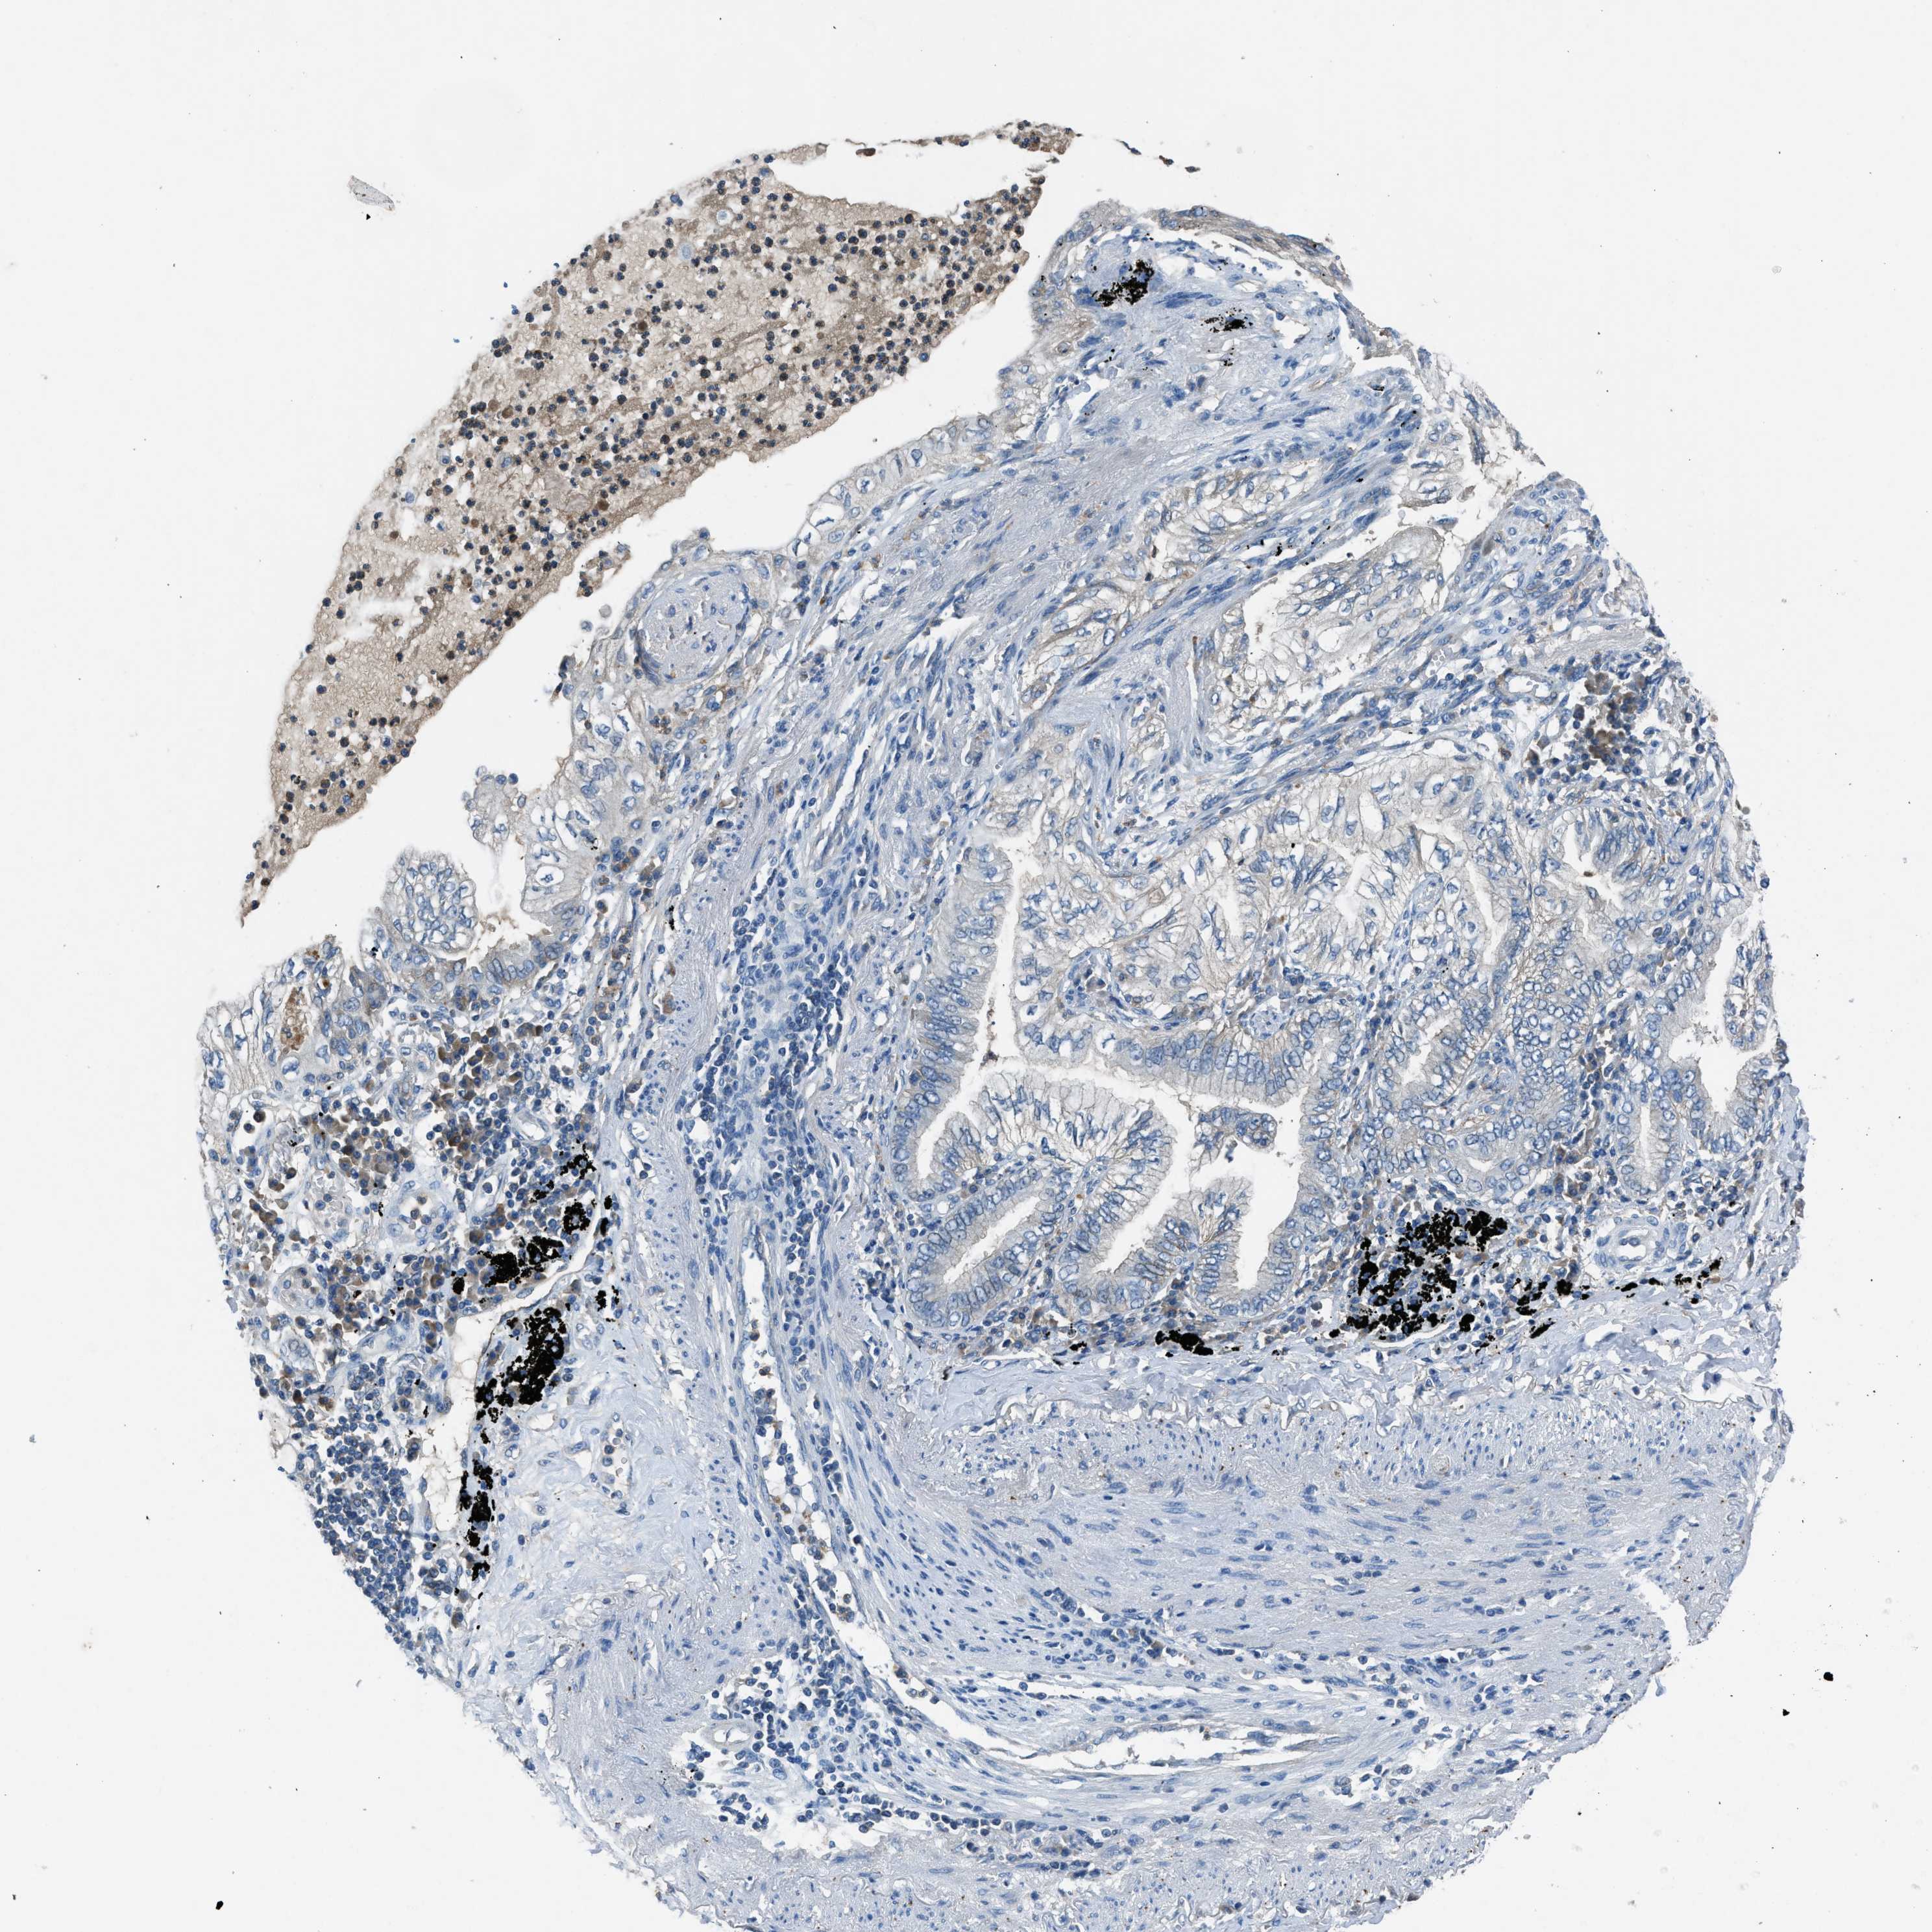

BMP1 is validated prognostic, high expression is unfavorable in Lung Adenocarcinoma (validation)

Best expression cut offi

When clicking on this number, the vertical dashed line indicating cut-off, the interactive survival plot, and the Kaplan-Meier curve will be adjusted to show results based on the best expression cut-off.

: 8.46

Median expressioni

: N/A

Median follow up timei

P scorei

N/A

5-year survival highi

For melanoma and glioma, 3-year survival is shown.

5-year survival lowi

Average pTPM 9.7

Number of samples 105